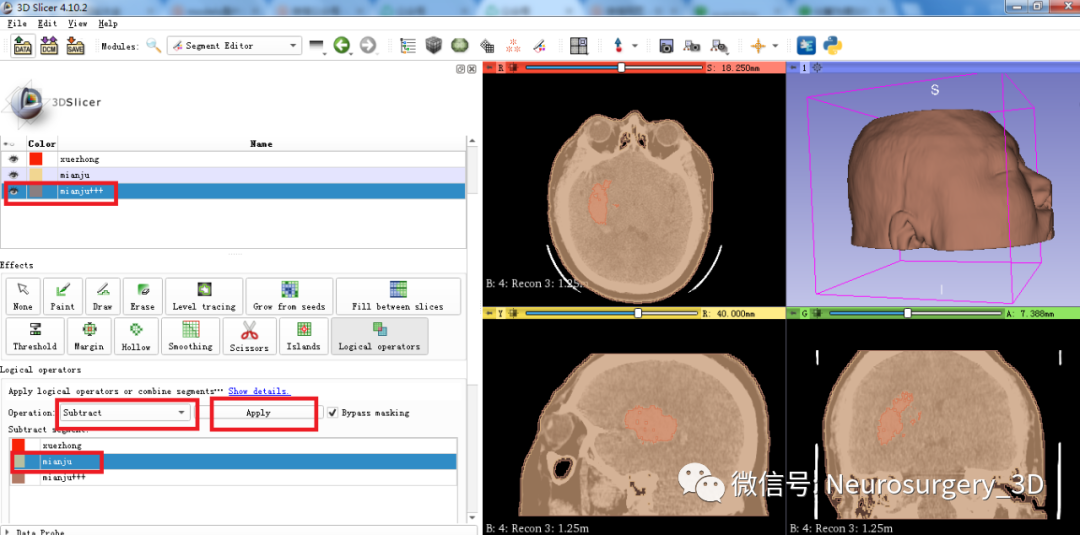

3、利用Logical operators逻辑运算模块中相减功能得出头颅面具模型。

二)利用Logical operators逻辑运算模块的复制、相减功能生成面具模型